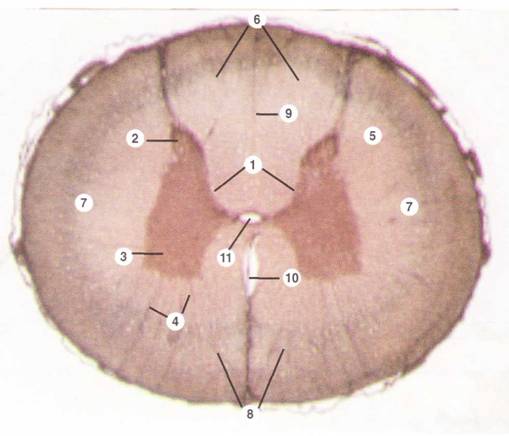

1 — серое вещество спинного мозга: на поперечном разрезе имеет форму бабочки. Его части: а) задние рога (2): относительно узкие и длинные выступы; расходятся кнаружи; б) передние рога (3): более широкие и короткие выступы; в) боковые рога: небольшие выступы по бокам (имеются на уровне грудных, верхнепоясничных и крестцовых сегментов спинного мозга). 4 — перегородки (септы): отходят от серого вещества в белое многочисленными лучами. Образованы отростками глиальных клеток. 5 — белое вещество: совокупность нервных миелиновых волокон. Его части: 6— задние канатики (содержат восходящие пути); 7 — боковые канатики (восходящие и нисходящие пути); 8 — передние канатики (нисходящие пути). 9 — срединная перегородка между задними канатиками; 10 — срединная вырезка между передними канатиками; 11 — центральный канал: выстлан эпендимой.